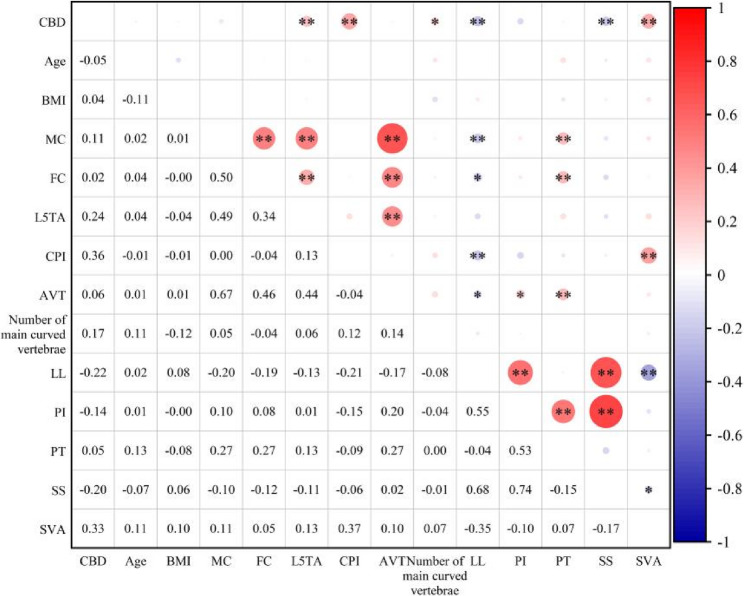

Pearson correlation analysis demonstrated substantial correlations between L5TA, CPI, the number of major curve vertebrae, LL, SS, and SVA with CBD (p < 0.05). Significant correlations were also determined among CPI, LL, and SVA. No significant correlations were found between AVT, MC, FC, PI, and CBD (refer to Table 2; Fig. 3).

Table 2: Pearson correlation analysis

| r | BMI(kg/m2) | Age(°) | MC(°) | FC(°) | L5TA(°) | CPI(°) | AVT(cm) | Number | LL(°) | PI(°) | PT(°) | SS(°) | SVA(cm) |

|---|---|---|---|---|---|---|---|---|---|---|---|---|---|

| CBD(cm) | 0.044 | −0.051 | 0.105 | 0.015 | 0.241** | 0.357** | 0.056 | 0.174* | −0.220** | −0.137 | 0.054 | −0.202** | 0.327** |

Abbreviations: CBD Coronal Balance Distance, BMI Body Mass Index, MC Major Curve, FC Fractional Curve, L5TA L5 tilt angle, CPI Coronal pelvic inclination, AVT apical vertebra translation, LL Lumbar lordosis, PI Pelvic Incidence, PT Pelvic Tilt, SS Sacral Slope, SVA Sagittal Vertical Axis, Number Number of main curved vertebrae

** indicates significance at the 0.01 level (two-tailed, p < 0.01); * indicates significance at the 0.05 level (two-tailed, p < 0.05)

Further stepwise linear regression analysis indicated that L5TA (R²=0.204, p < 0.05), CPI (R²=0.128, p < 0.05), and SVA (R²=0.172, p < 0.05) substantially influenced CBD (scatter plot demonstrated in Fig. 4).